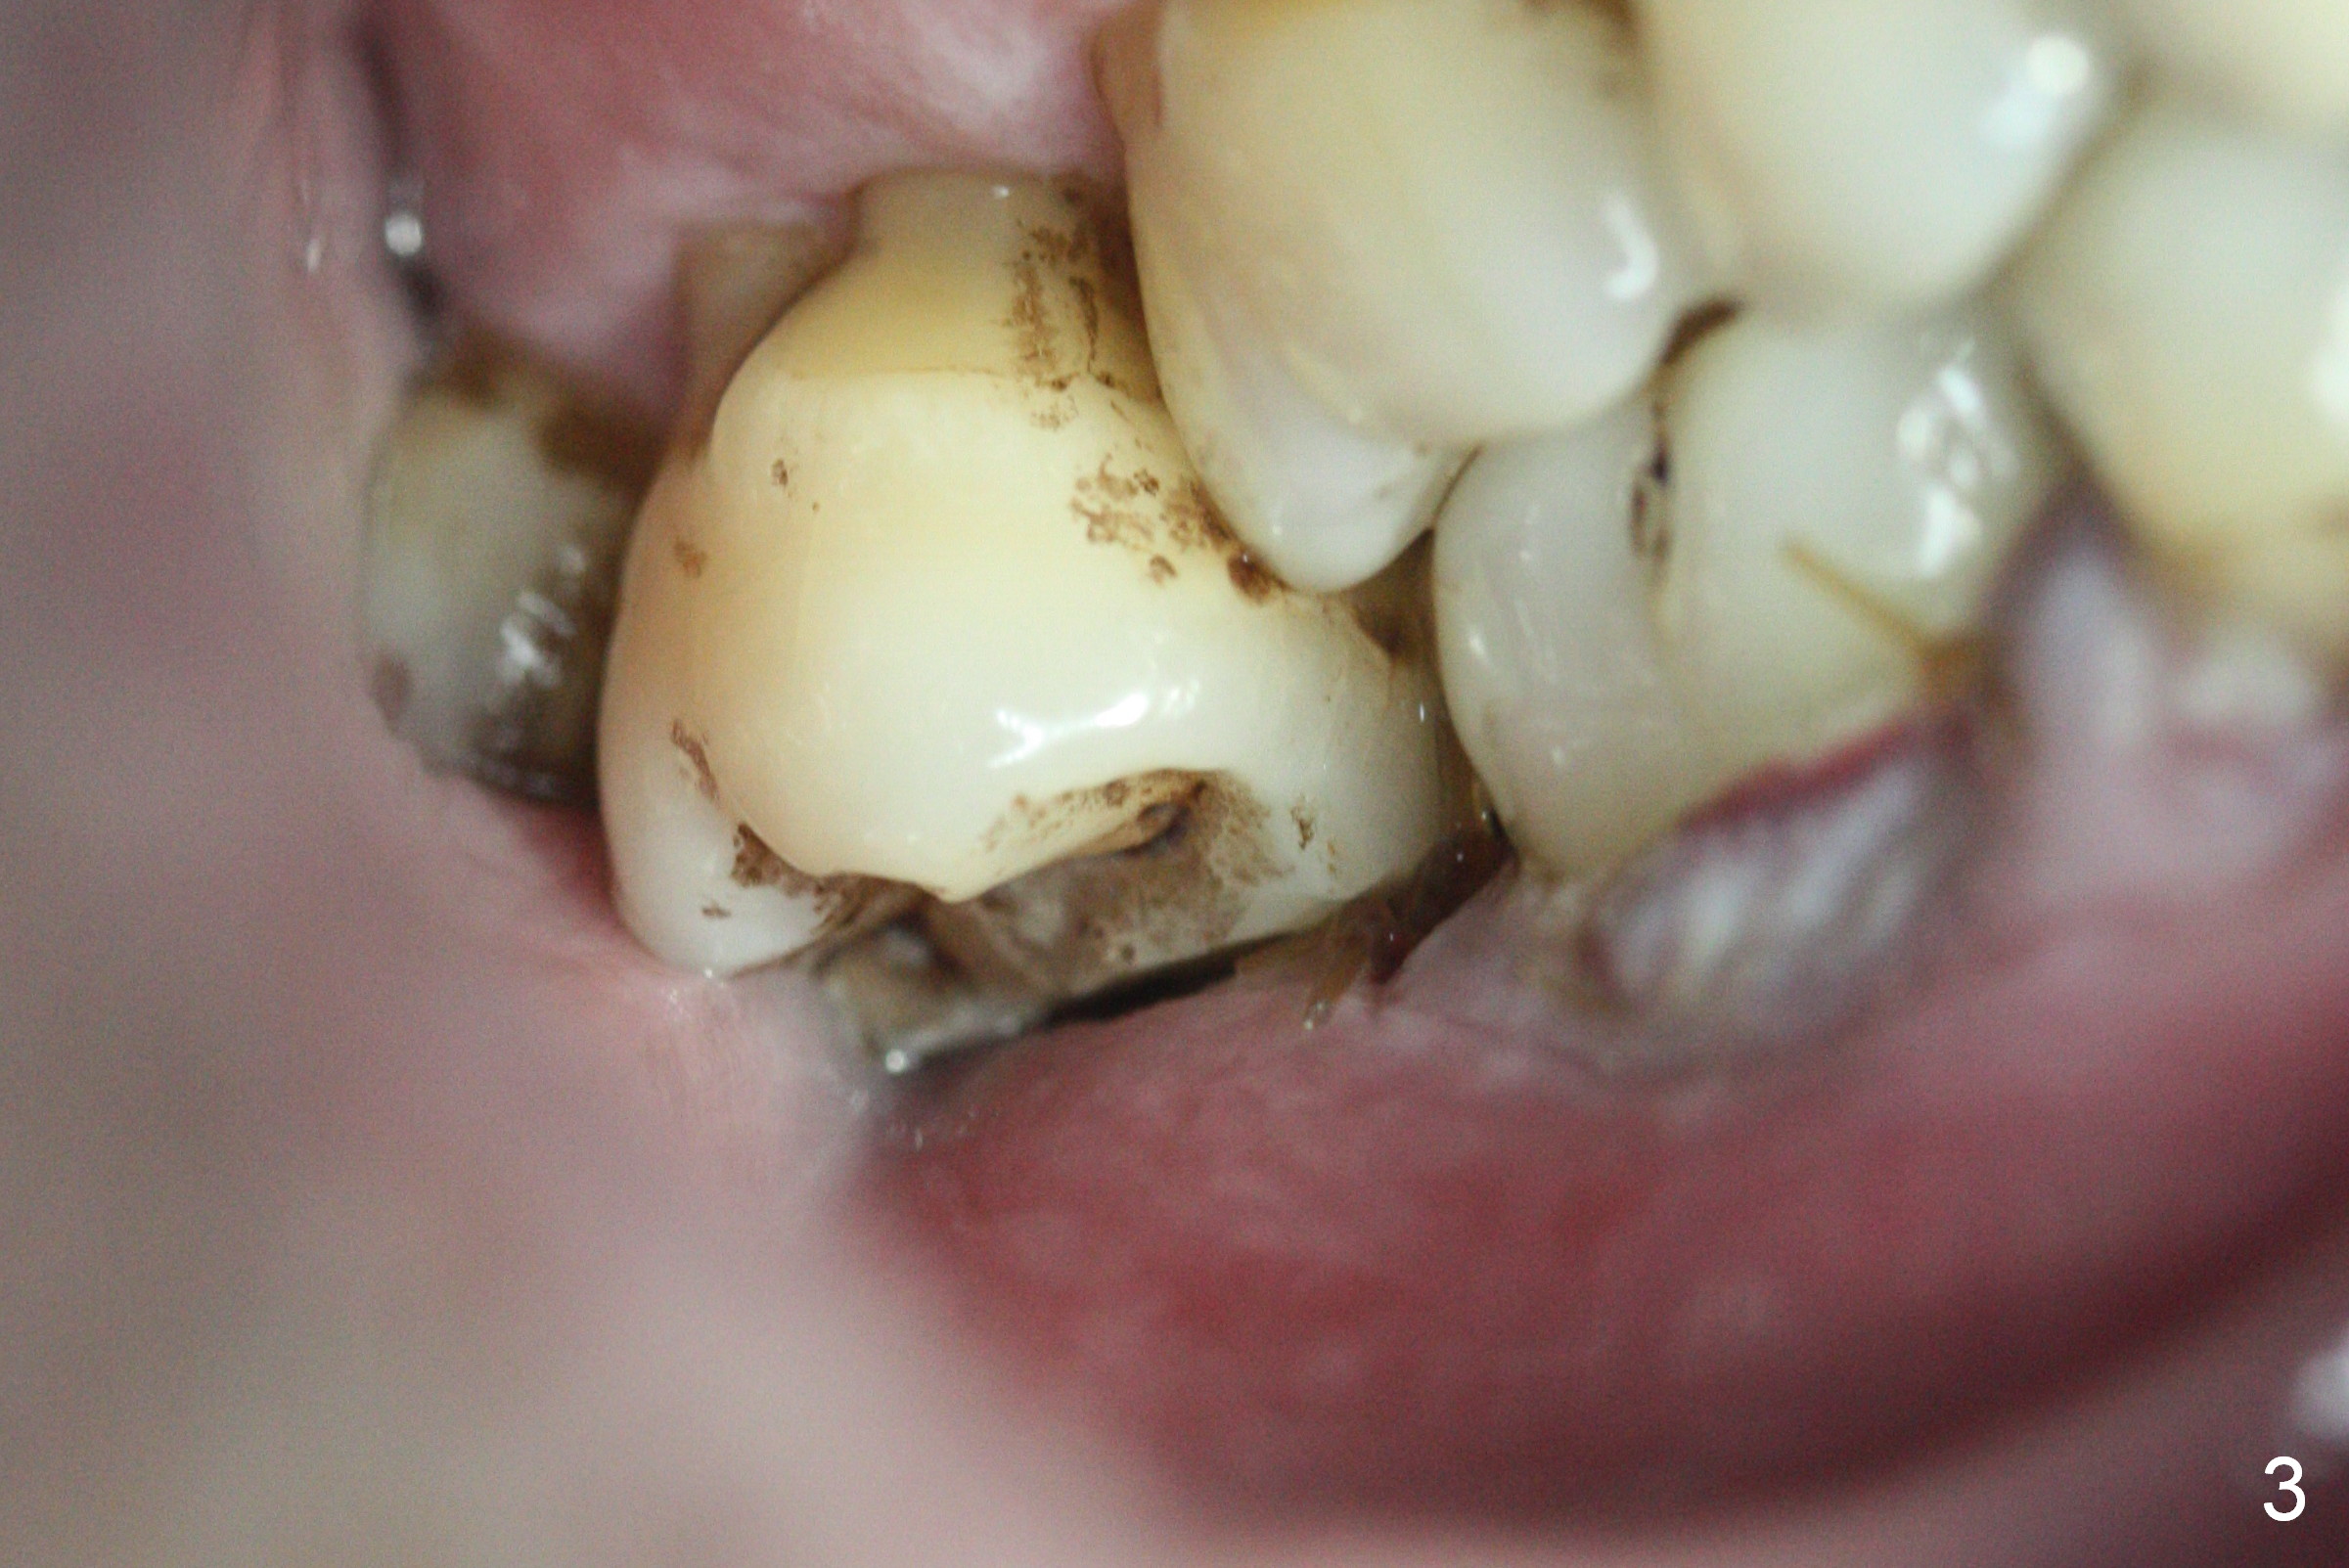

Two days post #31 implant placement, the patient returns for orthodontic intrusion of the tooth #2 with mini-implants (Fig.1). The palatal cusps have been trimmed (Fig.2 ^), since they almost contact a healing abutment at #31(*, Fig.3). Two mini-implants are to be placed mesiobuccal and distopalatal to the affected tooth. After minimal injection of Lidocaine, a 1.6x6 mm Tomas implant is placed in full length mesially (Fig.4), while the other (1.6x8 mm) half way (Fig.4). Following change in implant site mesially (Fig.6 >), the implant is half inserted (Fig.5). It appears that the tip of the distal implant is toward the tooth #1 (Fig.5). After withdrawing the implant partially, it is re-directed to apparently ideal trajectory (Fig.7). Ideally the mesial implant (Fig.8) should have been placed partially initially (Fig.4,5,7) so that the trajectory could have been able to be changed.